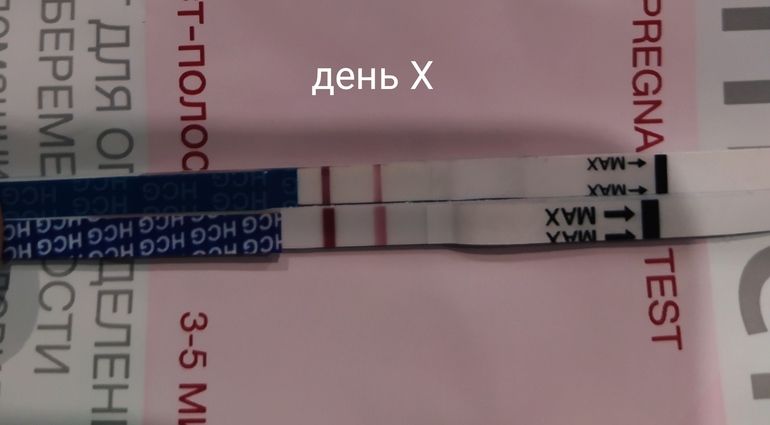

Здравствуйте, последние месячные были с 12.12.2022 по 16.12.2022, тест на беременность 9.01.23, подскажите пожалуйста, Ваше мнение, зачатие было в конце декабря допустим с 25 по 27 или 1-го января? За ранее спасибо!

Вы уже спрашивали,в декабре зачатие было,в январе не могло быть,вам бы на 16 дпо не нашли пя 7 мм с жм,это как минимум 3 недели от зачатия было уже

Лимоночка, Нашлась фотография это было 9 января, плохо видно правда, посмотрел в интернете динамику тестов это вроде как 13-15 дпо

Лимоночка, Нашлась фотография это было 9 января, плохо видно правда, посмотрел в интернете динамику тестов это вроде как 13-15 дпо

Вот эти тесты один 9 Января вечером, другой 11 января и тоже вечером

Вот эти тесты один 9 Января вечером, другой 11 января и тоже вечером

Елена Ивановна , 9 января уже судя по тестам 15 дпо точно было,вот мои тесты хгч -475 и 15 дпо